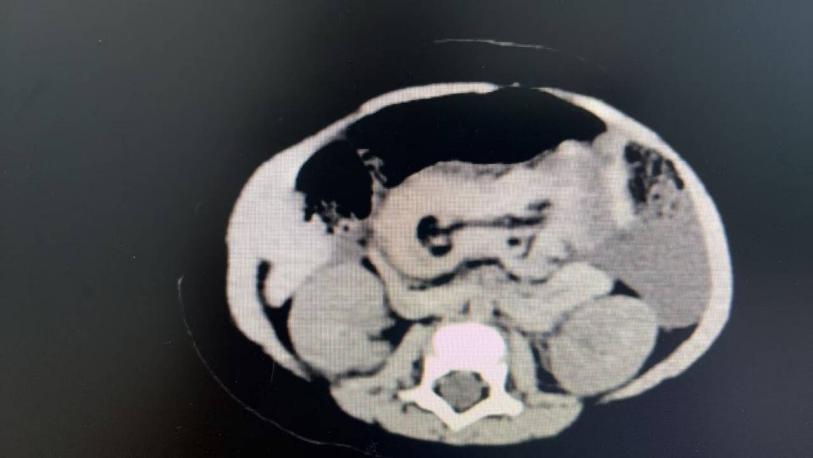

2  患兒術(shù)前CT